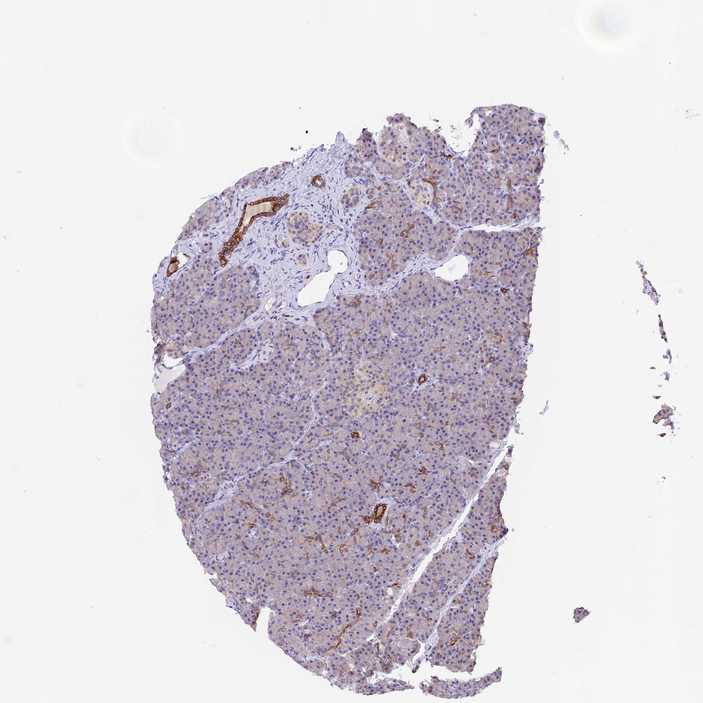

PANCREAS - Antibody stainingi

Antibody staining in the annotated cell types in the current human tissue is reported as not detected, low, medium, or high, based on conventional immunohistochemistry profiling in selected tissues. This score is based on the combination of the staining intensity and fraction of stained cells.

Each image is clickable and will lead to virtual microscopy that enables deeper exploration of all samples and also displays staining intensity scores, fraction scores and subcellular localization as well as patient and tissue information for each sample.

Antibody HPA042791

Exocrine glandular cells Medium

Pancreatic endocrine cells Not detected